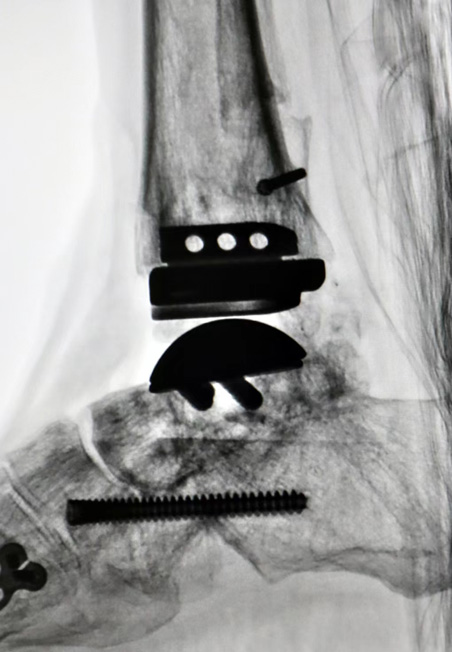

为最大限度提升术后效果,梁晓军为患者进行了全面完善的术前检查和准备。2月28日,肖某玲迎来了手术日。手术打开已经生长在一起的骨头,将原来的内固定取出,重新松解周围软组织、定位踝关节开放截骨线,最后将人工假体成功植入。“融合术后原来的两块骨头就变成一块了,要重新找到关节面,精确打开,再松解周围组织,手术要求非常高,好在手术顺利完成了。”梁晓军说,术后,肖某玲的踝关节就可以重新活动了。(卫晓康)